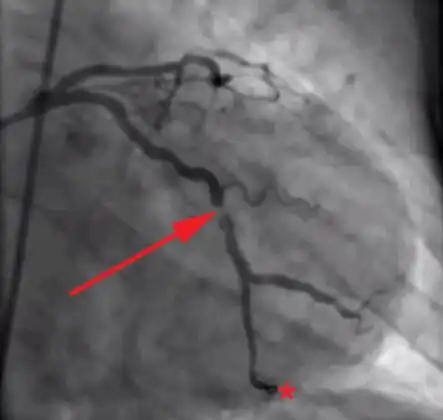

Angiographic image showing extensive LAD thrombosis -

Coronary angiography of an MI patient